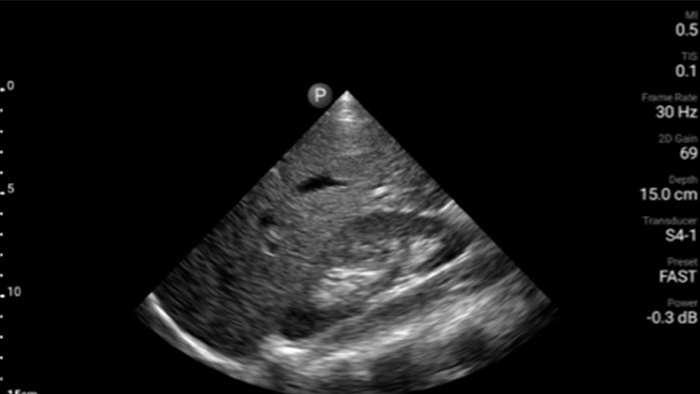

Lumify handheld ultrasound offers images that enhance diagnostic confidence.

See more when it counts

Lumify can help you make real-time decisions with more confidence, from assessment to recovery. Reveal the subtle details of an image, uncover enriched tissue definition with multiple angles and much more.

Emergency medicine